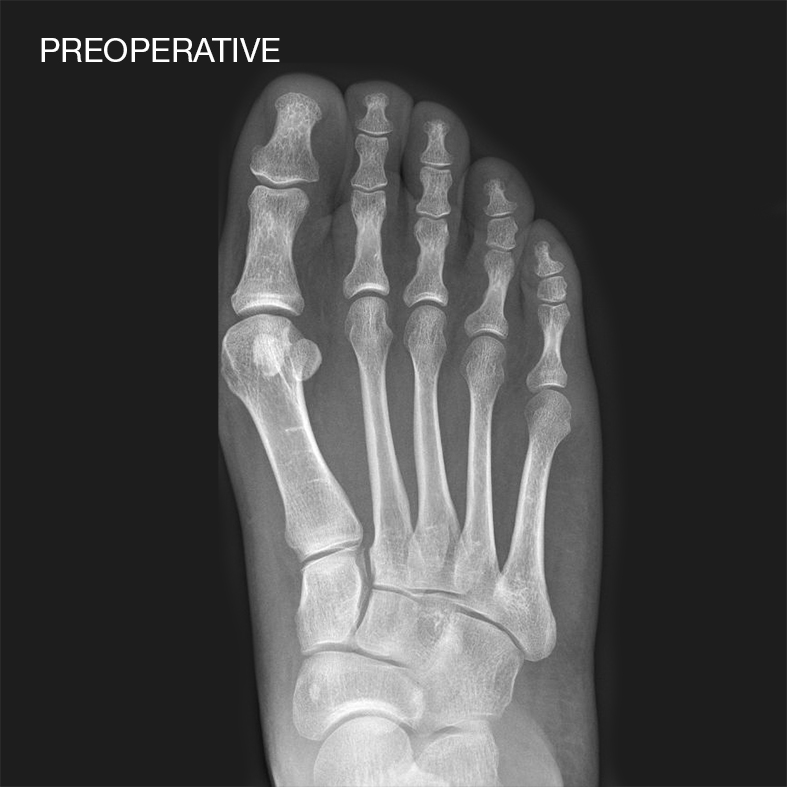

Case reports with Shark Screw®

Shark Screw® can be used in the space of Foot & Ankle (e.g. bunionectomy, MTP1 fusion, Hammertoe correction, IP-Fusion, TN-Fusion, Lapidus Arthrodesis, Lisfranc Joint Fusions, Jones Fx, Weil Osteotomies, DIP Fusions, Non-Unions, Medial Malleolus Osteotomies, Calcaneus Osteotomies, Subtalar Fusions etc.). Shark Screw® can be also utilized in various indications in Hand & Wrist surgery (e.g. DIP and PIP Fusions, MCP1 Arthrodesis, Scaphoid Fx and Non-Unions, Metacarpal Fusions, Four Corner Fusions, Distal Radius Fx etc.)